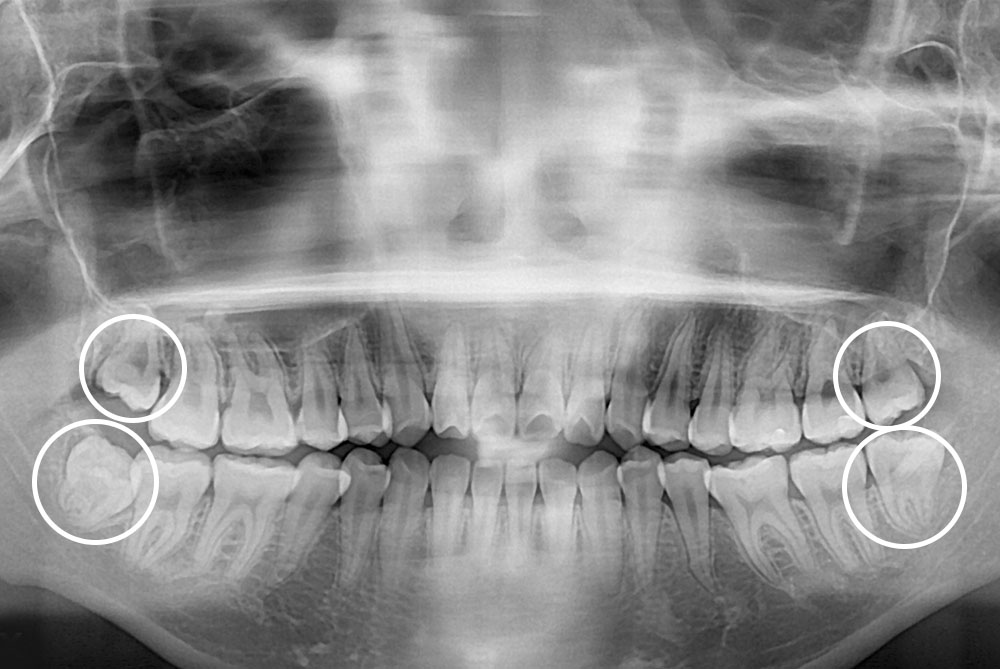

[사랑니] 매복 사랑니 발치

치료후 : 2019-03-11